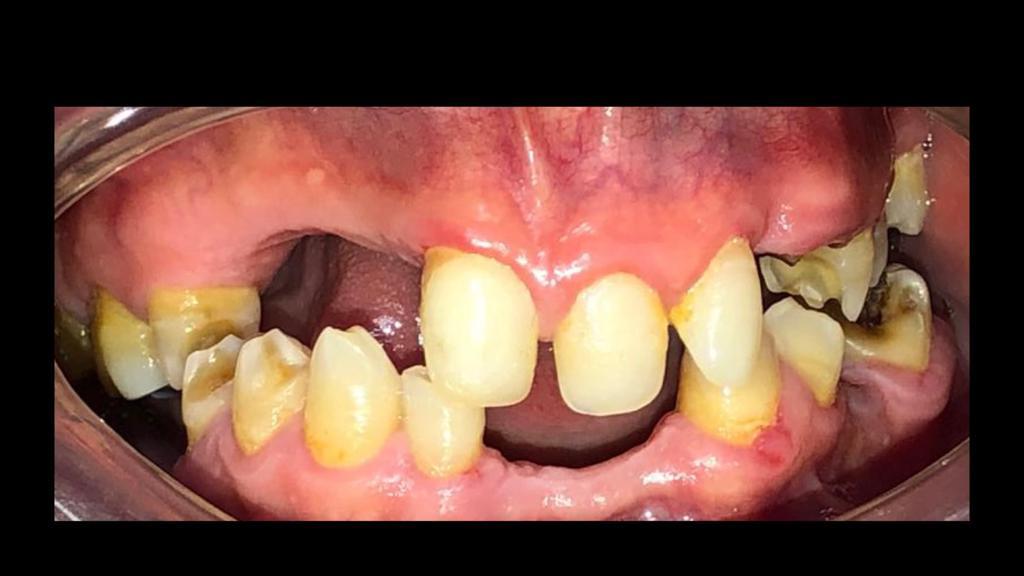

Fase 1: Diagnóstico inicial de rehabilitación oral

Fase 1

Rehabilitación Oral - Diagnóstico

Estado inicial del paciente con ausencia dental severa en maxilar inferior, afectando función masticatoria y estética.